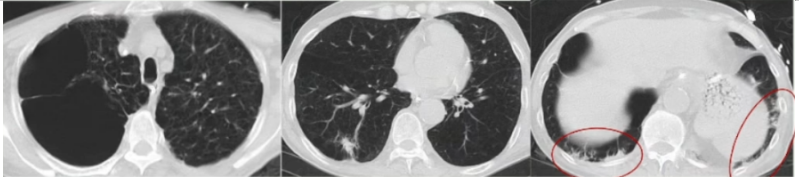

床旁支气管镜:隆突锐利,左右各叶支气管可见少量黏稠白色分泌物,予充分吸引,未见明显痰栓,各叶段予生理盐水肺泡灌洗,回收灌洗液(BALF),送检微生物培养。D-二聚体0.98 mg/L(胃内容物隐血阳性,预防性抗凝暂未实施,物理预防VTE)。考虑出现人机不协调可能是气道痉挛所致。调整呼吸机参数,更换为容量控制+压力支持模式,设定VT 为350 ml;加用阿曲库铵肌松;气道雾化治疗频率更换为q4h;甲泼尼龙剂量调整为40 mg q12h。调整后气道峰压下降至22 cmH2O。复查血气分析:pH 7.343,PaCO2 64.5 mmHg,PaO2 152 mmHg,氧合指数381 mmHg,乳酸1.5 mmol/L。患者呼气相延长好转,气促症状改善。2024年1月23日20:07,患者入院46 h,气促较前加重,哮鸣音明显,RASS评分-1分。复查血气分析:pH 7.206,PaCO2 104 mmHg,PaO2 59 mmHg,HCO3- 41.4 mmol/L,乳酸0.8 mmol/L。复查胸片:未见右侧新发气胸,左侧气胸未见进一步吸收,炎症不明显(图3)。予加深镇静镇痛。调整呼吸机参数为SIMV+PSV。1月23日22:04血气分析:pH 7.276,PaCO2 86.8 mmHg,PaO2 71.7 mmHg,HCO3- 40.4 mmol/L,乳酸1.3 mmol/L。1月24日09:34血气分析:pH 7.335,PaCO2 80 mmHg,PaO2 67.7 mmHg,HCO3- 40.1 mmol/L,乳酸1.3 mmol/L。(1)患者二氧化碳潴留反复加重的原因是什么?气道痉挛缓解困难的原因是什么?(2)并发气胸加重?——复查胸片可以排除这种可能。(3)并发肺栓塞?——D-二聚体基本正常,临床表现也无明显证据。1月24日BALF培养结果提示为烟曲霉。是否是致病菌?该患者危险因素符合:①慢性病基础(慢阻肺);②糖皮质激素应用史;③广谱抗生素应用史。不符合之处:①体温正常;②炎症指标正常;③胸部影像学未见新发感染征象;④外周血G试验/GM试验正常。1月24日加用伏立康唑片剂0.2 g q12h鼻饲,复查胃内容物隐血阴性,VTE评分5分(高危),根据体重调整剂量后加用依诺肝素3000 U预防性抗凝治疗。甲泼尼龙减量至40 mg qd,雾化减至q12h。继续有创呼吸机辅助通气,动态调整呼吸机参数,镇静镇痛,肌松。完善lgE、过敏原检测;动态复查胸片、血气分析、炎症指标。检查结果回示:IgE 37 lU/ml;吸入物+食入物过敏原阴性。1月26日复查血常规+hs-CRP:WBC 6.4×109/L,NEU% 92.0%,EOS% 0.0%,Hb 124 g/L,PLT 201×109/L,hs-CRP 9.24 mg/L。呼吸机参数:SIMV+PSV, PCV/PSV 20 cmH2O, PEEP 10 cmH2O, VT 200~500 ml。1月25日血气分析:pH 7.402,PaCO2 70.1 mmHg,PaO2 94.4 mmHg,氧合指数270 mmHg,乳酸1.1 mmol/L。1月26日血气分析:pH 7.431,PaCO2 67.7 mmHg,PaO2 80.5 mmHg,氧合指数230 mmHg,乳酸1.4 mmol/L。1月27日血气分析:pH 7.462,PaCO2 60.8 mmHg,PaO2 88.2 mmHg,氧合指数252 mmHg,乳酸1.6 mmol/L。1月27日复查胸片:与1月24日胸片对比,气胸未进一步加重,亦未见新发感染病灶(图4)。患者气道痉挛仍然存在,1月27日试停肌松后气道痉挛加重,人机不协调,脱机困难,1月29日出现发热(图5),气道内分泌物未见增多。抗感染药物已经覆盖了烟曲霉,患者为何出现发热症状——口服伏立康唑血药浓度不足?合并其他微生物感染?出现脓毒血症?寻找依据:查伏立康唑血药浓度为5.26 μg/ml(正常范围)。1月29日复查血常规:WBC 6.7×109/L,NEU% 89.3%,EOS% 0.0%,Hb 127 g/L,PLT 260×109/L,hs-CRP 3.66 mg/L。PCT、IL-6均正常,完善血培养【5~7天,等待结果】。经验性加强抗感染,停用哌拉西林他唑巴坦,更换为美罗培南。BALF送检NGS进一步明确致病菌。1月31日复查胸片:没有明显的新发感染迹象(图6)。送检BALF NGS 1天后结果回报:烟曲霉(序列数2272),乙型流感病毒(序列数47)。伏立康唑改为针剂0.2 g q12h,联合卡泊芬净50 mg qd(首剂70 mg),联合两性霉素B脂质体50 mg biw雾化;加用玛巴洛沙韦抗病毒。患者气道痉挛明显,气胸风险大,床边备胸膜切开包。复查血常规+hs-CRP:WBC 7.8×109/L,NEU% 86.6%,Hb 130 g/L,PLT 198×109/L,hs-CRP 1.0 mg/L。血培养回报阴性(双瓶双侧)【脓毒血症依据不足】。经过上述治疗,患者体温较前下降,支气管镜下气道分泌物较前减少,气道痉挛部分缓解,呼吸机参数改善,试停肌松。1月31日血气分析:pH 7.423,PaCO2 59.9 mmHg,PaO2 75 mmHg。2月1日血气分析:pH 7.420,PaCO2 58.6 mmHg,PaO2 81.2 mmHg。2月4日患者再次出现发热,体温最高38.1℃,气道痉挛加重,血气分析提示二氧化碳潴留加重,PaCO2 71.6 mmHg。复查炎症指标:WBC 12.2×109/L,NEU% 93.2%,hs-CRP 32.97 mg/L,PCT 0.068 ng/ml,IL-6 19.8 pg/ml。复查胸片提示两肺炎症改变,右肺下野团片影(图7)。复查BALF细菌培养:纹带棒状杆菌>103CFU/ml。真菌培养:无真菌生长。复测伏立康唑血药浓度3.03 μg/ml。纹带棒状杆菌是定植,还是致病?2月4日复查胸部CT:与入院时CT相比,出现两下肺斑片渗出影(图8)。考虑患者合并细菌感染。